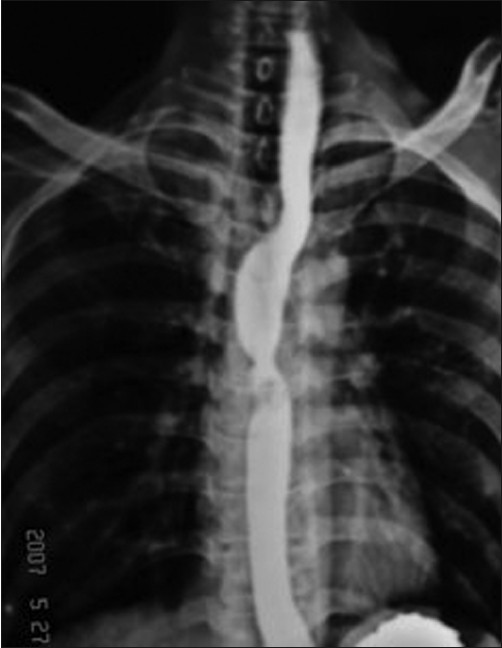

1. بلع الباريوم لتصوير الطريق المعدي المعوي العلوي.IndianJournalofCancer_2011_48_1_112_76630_u2

2. تصوير الصدر بالأشعة السينية.